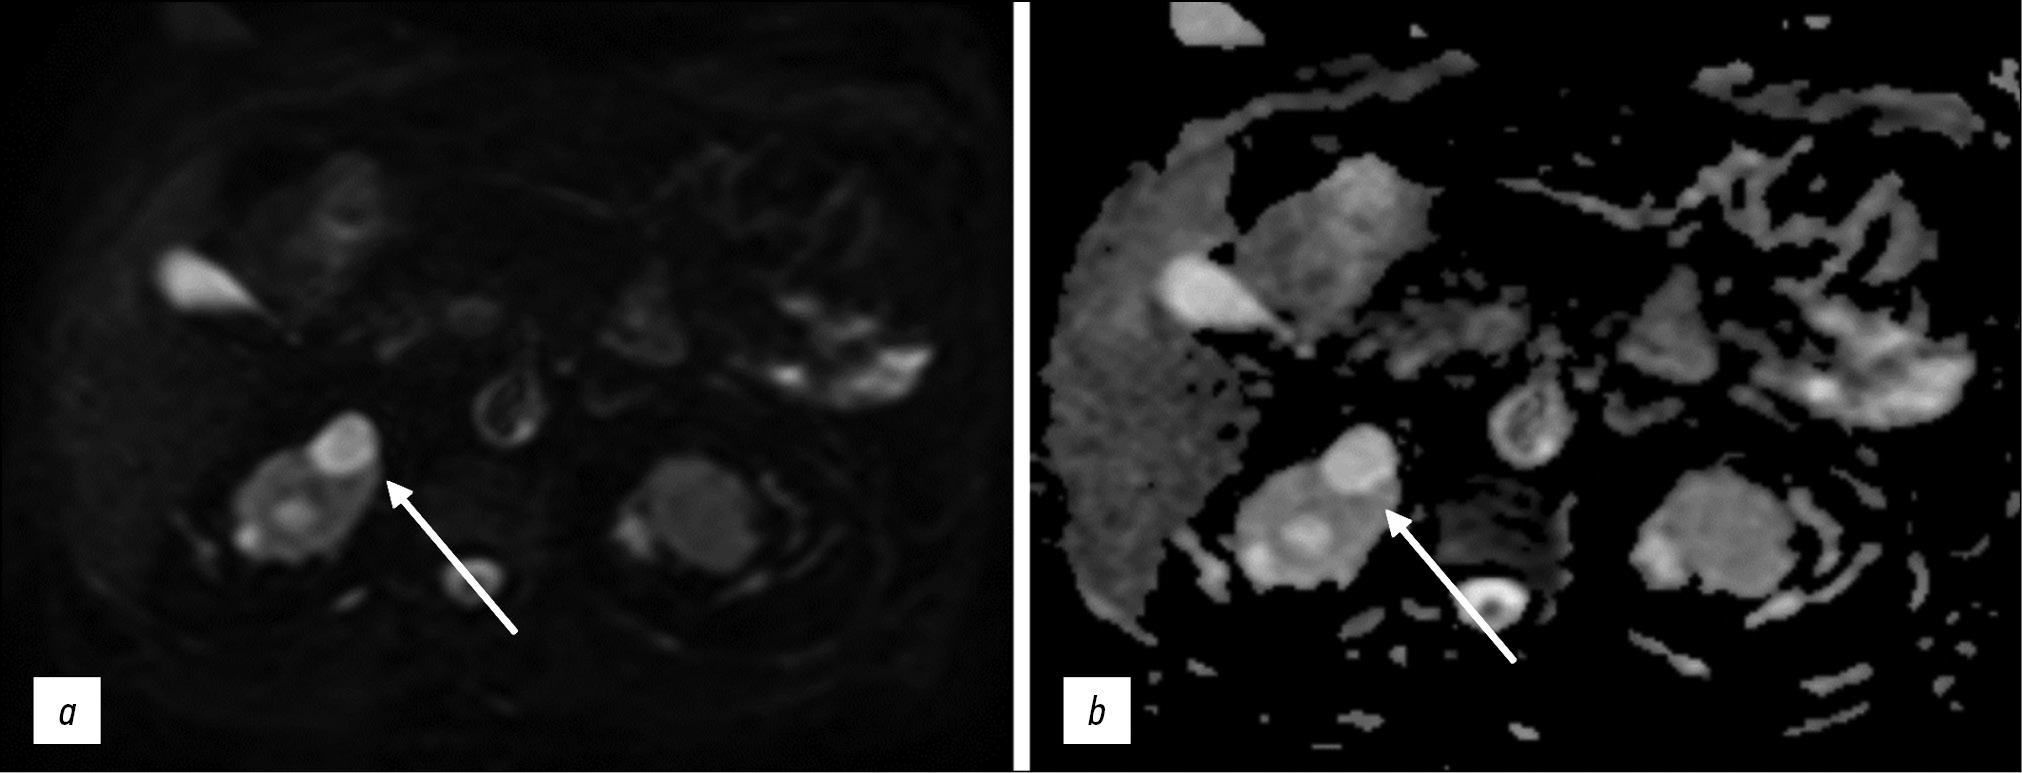

DWIs are based on differences in the movement of water molecules (diffusion) in the extracellular and intracellular spaces and are used for visualization without exogenous contrast agents. This technique allows for quantitative and qualitative analyses of not only cell density but also cell membrane integrity, making it a type of functional image assessment [10]. Therefore, it should be included in standard abdominal and retroperitoneal MRI protocols (Figs. 2 and 3).

Figure 2. Abdominal magnetic resonance imaging, simple renal cortical cysts (arrows): а a diffusion-weighted image; b map of the apparent diffusion coefficient. False restricted diffusion.

Figure 3. Abdominal magnetic resonance imaging, secondary hepatic lesions (arrows): а a diffusion-weighted image; b map of the apparent diffusion coefficient. True restricted diffusion.

DWIs were initially used to diagnose brain pathology, primarily strokes: signal changes in a given pulse sequence allow for the detection of ischemic changes long before they are visible on T2-WIs. DWIs are now used to diagnose various extracranial pathologies owing to advancements in high-amplitude gradients, multichannel surface coils, and parallel imaging.

Diffusion is proportional to cell density and cell membrane integrity: restricted diffusion is observed in tissues with increased cellularity or decreased extracellular fluid volume (e.g., some tumors and abscesses; Fig. 4) and in the presence of cytotoxic edema. Relatively free diffusion is observed in tissues with low cell density or when their membranes are damaged, such as cysts or necrotic tissues.